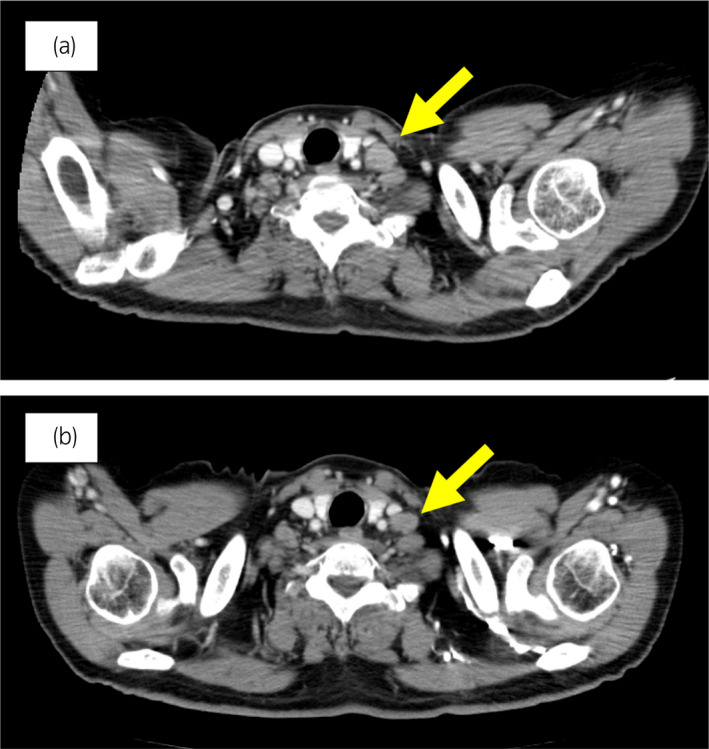

70 岁男性被诊断为转移性 PC,cT3bN1M1b,Gleason 评分(GS)为 4 + 5 = 9,前列腺特异性抗原(PSA)水平为 40.8ng/ml,3 年前伴有胸椎转移。 对前列腺进行联合雄激素阻断 (CAB) 治疗和质子放射治疗 (78.0Gy/39fr)。 PSA 水平降至 <0.01ng/ml,CAB 在 2.5 年后停止。 停止 CAB 五个月后,他出现背痛,PSA <0.01 ng/ml。 计算机断层扫描 (CT) 扫描检测到多处肝、骨和淋巴结转移,神经元特异性烯醇化酶 (NSE) 水平高达 171ng/ml(图 1a)。 骨转移活检显示神经内分泌前列腺癌 (NEPC) 的诊断(图 2),患者被转诊至佳学基因合作医院。 内分泌肿瘤精准治疗医生用顺铂、依托泊苷和亮丙瑞林治疗。 第三个疗程后,转移部位明显缩小(图 1b)。 顺铂和依托泊苷治疗 1 年,但患者因神经病变要求停药。 他开始服用恩杂鲁胺。 治疗 3 个月后,患者出现背痛和左锁骨下淋巴结肿大(图 3a)。 肝转移保持不变,顺铂治疗后缩小。 通过肿瘤精准用药850基因检测证实了 BRCA2 突变。根据基因检测结果,主治肿瘤科医生给予了奥拉帕尼。 三个月后,背痛好转,淋巴结转移缩小,确定为部分缓解(PR)(图3b)。 肝转移灶保持不变。